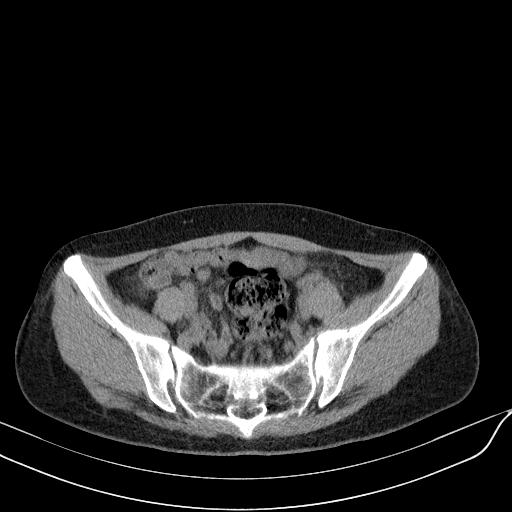

标题: CT23965:无外伤史,下腹痛 [打印本页]

标题: CT23965:无外伤史,下腹痛

肠道未准备,继续往下扫,乙状结肠占位不排除。建议钡灌或结肠镜检查。

乙状结肠占位不排除

未见明显异常改变,做个气钡双重造影除外一下结肠病变,无外伤史为啥不常规喝泛影葡胺水对比剂再扫ct呢?

肠道肿瘤,建议行钡剂灌肠检查。